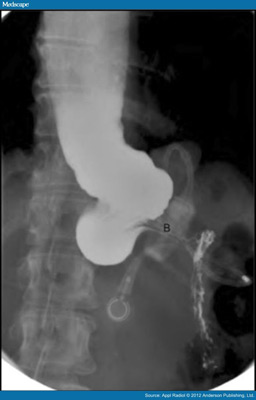

As time went by, most people became very comfortable with their gastric band and did not make the necessary medical visits. Gastric banding is not without risks. The band may get lose and slip up or down on the stomach in spite of initially good fixation. This may lead to near complete or complete blockage in the path of food resulting in frequent vomiting and unhealthy weight loss. A band that is too tight around the stomach may slowly erode through the wall of the stomach and appear inside. This may initially only present as pain, like an ulcer-type pain, but may lead to stomach bleeding and bloody bowel movements or vomiting, which can be very scary. Exposure of the band to the gastric contents may result in the infection of the entire tubing and the surrounding tissues. Even a well adjusted band will put an extra stress on the esophagus, which tries to push the food down into the stomach. The narrowing caused by the band presents a relative obstruction, which may lead to a condition called pseudo-achalasia, that is a condition characterized by damaged or complete loss of motility of the esphagus. All the above conitions may necessitate the removal of the band. Most of these do not develop from one day to the next, but slowly, over months to years. A regular, at least annual follow up with the surgeon is recommended who will periodically order x-rays to assess the position of the band and the health of the surrounding organs.

In certain scenarios repositioning of a displaced gastric band is a viable option, but removal of the band is unavoidable in case there is erosion or the esophagus has significant motilty problems. The band removal procedure usually takes less than an hour and it is done laparoscopically under general anesthesia. The body builds a significant aount scar tissue around the band and dissecting the band out of the scar takes most of the time during the operation.The scar tissue may result in distorsion of the stomach in the future. Conversion of gastric banding to other type of bariatric procedure is possible but the insurance coverage is not automatic and a thorough preparation is necessary prior to any such intervention.